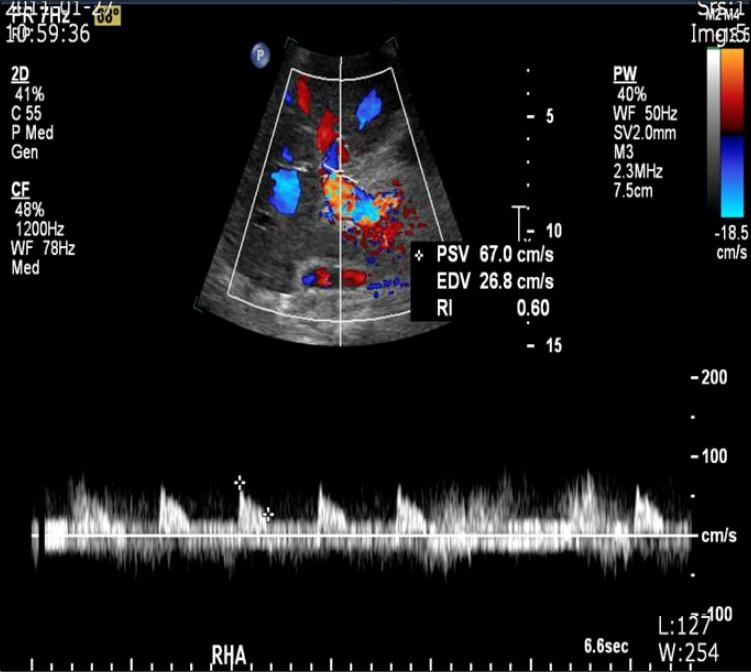

It is important that extrahepatic arteries are identified precisely at the time of graft procurement. We present a case where the accessory right hepatic artery of the liver was ligated leading to postoperative liver abscess formation in the liver graft. A forty-seven-year-old female patient diagnosed with liver cirrhosis underwent orthotopic cadaveric liver transplantation due to altered mentality. The donor graft showed a variant of the hepatic artery anatomy where an accessory right hepatic artery arose from the superior mesenteric artery. This artery was accidentally transected during procurement. Since the back bleeding test using perfusion fluid was good, the artery was ligated. Postoperative abdominal computed tomography scan revealed a 6 cm low attenuating lesion in the liver. The patient underwent conservative treatment. We believe that even small accessory arteries (1 to 2 mm) should be reconstructed whenever possible to avoid postoperative complications such as liver abscess.

在获取移植物时精确识别肝外动脉非常重要。我们报告一例病例,肝脏的副右肝动脉被结扎,导致肝移植术后肝脓肿形成。一名47岁诊断为肝硬化的女性患者因意识改变接受了原位尸体肝移植。供体移植物显示肝动脉解剖结构变异,一条副右肝动脉发自肠系膜上动脉。在获取过程中该动脉意外被切断。由于使用灌注液进行的回血试验良好,该动脉被结扎。术后腹部计算机断层扫描显示肝脏有一个6厘米的低密度病变。患者接受了保守治疗。我们认为,只要有可能,即使是小的副动脉(1至2毫米)也应进行重建,以避免术后并发症如肝脓肿。